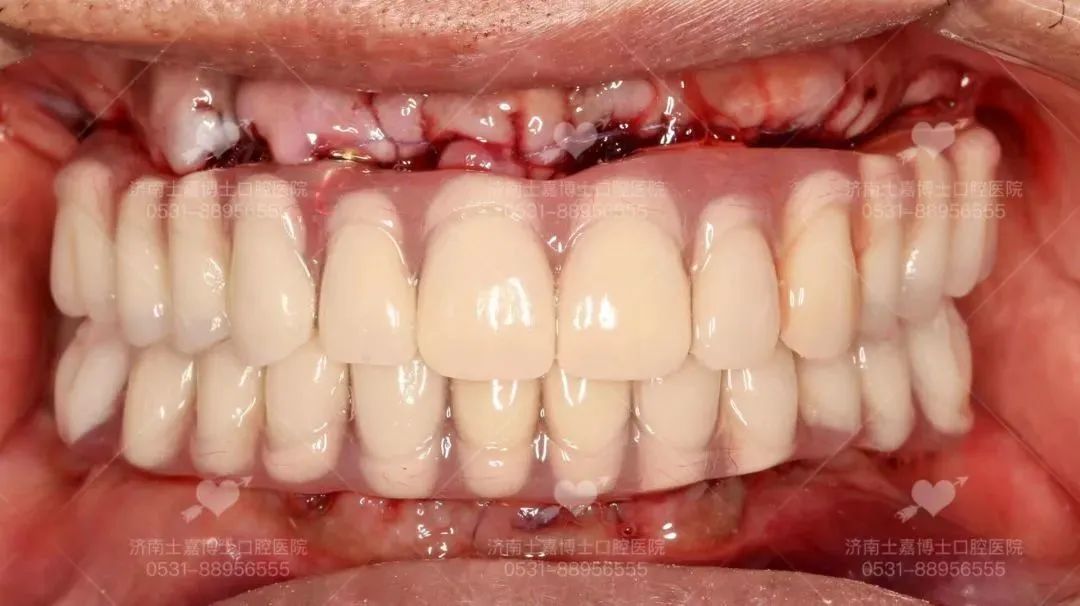

舒适化牙齿种植后 老人种植后牙齿状况 口腔X光片 术后的老先生很快恢复了意识,仍处在观察期的他已经迫不及待吃上肉包子,由衷的感叹:太好了~